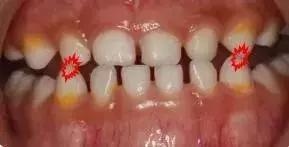

专业地说,儿童乳牙期“地包天”,就是乳下前牙咬合于乳上前牙唇侧,也叫乳前牙反颌。

简单说,就是下面牙齿把上面牙齿款到了,限制了上面牙齿和骨头的发育。

“地包天”的后果

儿童“地包天”很有阔能引起娃娃身心都受挫哦!牙齿不整齐、下巴总是往前伸,不仅看起来不好看,还要影响咀嚼功能、发音、颞下颌关节发育,最恼火滴是对好多娃娃心理健康影响大,搞得娃娃都没得自信了!

当娃娃越长越大,症状还可能加重,下巴前突,面型畸变,更严重的还可能会变成朱元璋一样的“鞋拔子脸”、“半月脸”!